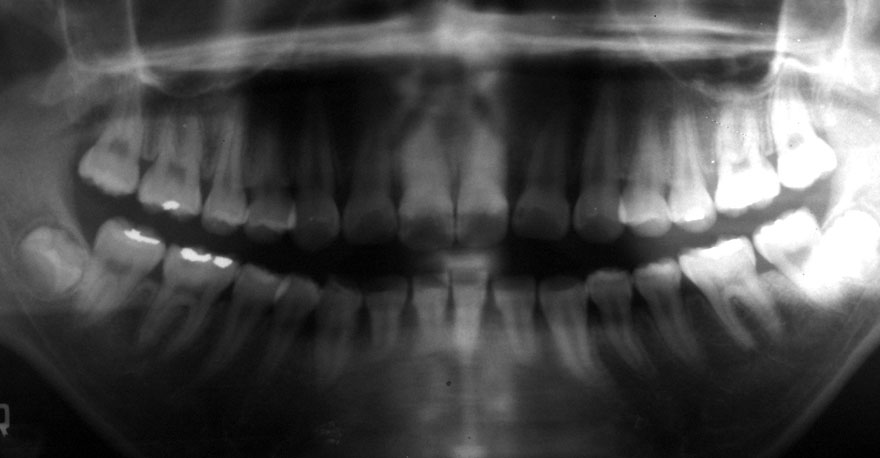

初診時 17歳 女性

20年後 37歳